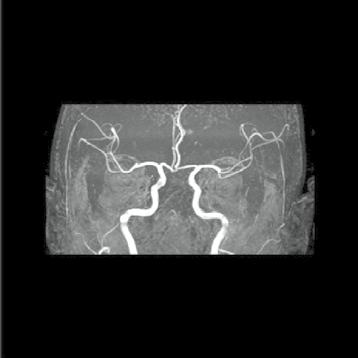

Muž, 61 let. Ischemie ve vertebrobazilárním povodí, dvakrát prodělal infarkt myokardu (IM), v anamnéze kardiomyopatie, hypertenze. Náhlá porucha vizu, nauzea, vomitus, hypakuze, vertigo, nemůže se sám postavit. Objektivní vyšetření: dezorientován, cerebelární syndrom vlevo, centrální vestibulární syndrom, levostranná hemiparéza.

Obr. A1.1–A1.4 Trombóza a. basilaris, akutní ischemické změny vertebrobazilárního povodí (pons, pedunculus cerebri medius dextra, parietookcipitální oblast).

Šipka v obrázku A1.2 – nezobrazilo se vertebrobazilární povodí